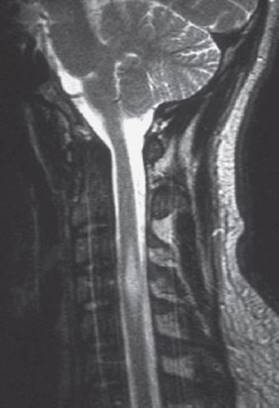

Cervical myelopathy is often due to degenerative narrowing of the spinal canal with resulting spinal cord compression. Patients with inflammatory diseases of the spine, such as rheumatoid arthritis, are at elevated risk. The initial presentation is often with (poly-)radicular deficits due to narrowing of the intervertebral foramina; as the spinal canal itself becomes increasingly stenotic, clinically evident spinal cord compression develops. Patients typically complain at first of paresthesiae in the fingers and impairment of the sense of touch (examination reveals astereognosis). The intrinsic muscles of the hands may become atrophic. Ultimately—or, rarely, as the sole manifestation—involvement of the long white matter tracts produces spastic paraparesis, enhanced reflexes, and pyramidal tract signs. Neuroimaging is essential for the establishment of the diagnosis; MRI is best (Fig. 7.8). Neurosurgical decompression of the spinal canal, possibly with spinal stabilization (fusion) at the same procedure, generally arrests the progression of the neurological deficits.

Fig. 7.8 Myelopathy in cervical spondylosis. The T2-weighted MR image reveals narrowing of the spinal canal at C5/C6 and C6/C7 both anteriorly and posteriorly because of degenerative spondylotic changes. A signal abnormality in the spinal cord below C6/C7 indicates a lesion induced by compression.